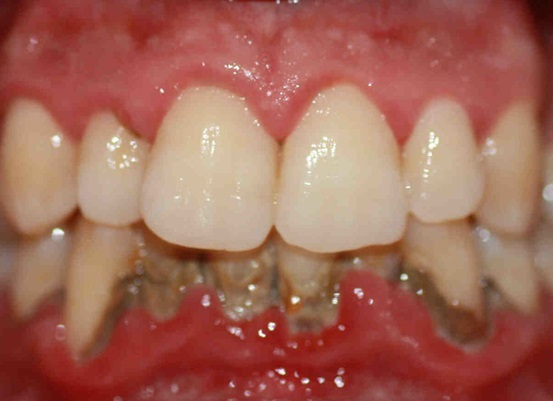

CORROSIONES DE LOS METÁLES PESADOS

Bajo corrosiones entendemos signos de disgregación electrolítica o descomposición. Las vemos en coronas y puentes donde se emplean aleaciones poco nobles o en presencia de metales diferentes, especialmente en los sitios o puntos de soldadura. Es posible reconocerlas a simple vista o al sondeo por la porosidad de la superficie metálica sospechosa.

Se sabe que estos metales corrosionados pueden desencadenar desde los dientes estados patológicos idénticos a los que producen los focos de cualquier índole. Todos estos tratornos se deben a que los iones de los diversos metales se sepraran, se disuelven y forman en el tejido de la encía complejos metalo-protéicos que pueden alergizar el organismo.

BIMETALES

Cuando se dice que en una boca hay bimetales, se da a entender que esa boca presenta metales diferentes entre sí como por ejemplo: oro, amalgama o unidades de metales blancos como acero, etc. Su componente focal activo se basa en que entre los susodichos metales surgen tensiones eléctricas en el sentido de diferencias de potencial y todas estas "en su totalidad" pueden llegar a constituir un campo interferente con todas las molestias a distancia, que le son características. Según E. THIELEMANN ni siquiera es necesario que haya en la boca metales diferentes; una diferencia de potencia también puede presentarse cuando las aleaciones son hetereogeneas, como amalgama o cuando aleaciones de oro y acero inoxidable, por lo mal elaboradas, se han tornado hetereogeneas.

DIENTES VIVOS PERO ENFERMOS

Es posible que el diente que aun vive adquiere carácter de foco. La afectividad focal de dientes semejantes se da cuando cierta clase de influencias caen sobre el diente, tales como insultos mecánicos, traumáticos, térmico físicos, eléctricos, bacteriano-infecciosos, tóxicos químico medicamentosos, abrasiones fuertes, caries profundas -como se ven amenudo en esclerosis multiple- debajo de obturaciones de metal, de plástico, silicatos que conllevan a alteraciones inflamatorias o degenerativas de la pulpa, lo que por su parte conduce a descomposición protéica y formación de antígenos (HILLER, DITTMAR y otros).

Esto puede ser observado especialmente en dientes vitales con corona, preferentemente si se los utiliza para ferular. El solo tallado del diente como pre-acondicionamiento para coronarlo es una "herida" (REBEL) que puede tener como consecuencia una lesion pulpar.

Si el diente en cuestión visto en forma odontológica -está bien tallado la probabilidad de una irritación quizás irreversible de su pulpa es mucho mas grande, si está mal tallado le queda la corona obligatoriamente defectuosa, esto significa que los bordos de la corona se sobrepasan y cae la encía en el estado de una inflamación crónica formando consecuencialmente un campo de interferencia con efectos patológicos a distancia.

Para no salirnos del meollo del problema debo insistir que no es la caries la que en los casos citados tiene un efecto focal sino la alteración patológica de la pulpa. El substrato anatomo-patológico de estos procesos, que clínicamente no suelen llamar mucho la atención, se basa en toda una serie de alteraciones patológicas caracterizadas por el hecho de que en su evolución el tejido pulpar se destruye y es reemplazado solo en parte por tejido conectivo. Este "cuadro clínico" fue descrito por HAUPL. RAAB y otros como "flema pulpar" (PHLEGMASIE). Dijimos en aquel entonces que este proceso no constituia ninguna enfermedad "sui generis" sino que desde el punto de vista evolutivo dicha reacción era la única expresión morfológica con que la pulpa le respondía a toda una cadena de diferentes irritaciones. El suceso patológico se inicia siempre con molestias circulatorias locales. En casos así la sola alteración pulpar puede adquirir carácter de foco. Estos son los motivos de cuando y porque dientes vivos pueden jugar un funesto papel. El principio común del diente con pulpa muerta y del diente aún vivo pero enfermo se basa pues en la sensibilización del cuerpo por descomposición protéica v.gr. por detritus resultante de dicha descomposición. Para subrayar lo expuesto un ejemplo: